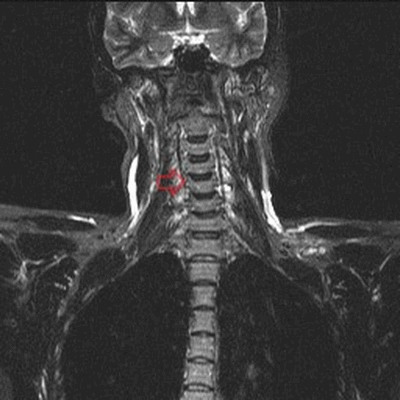

МРТ шейного отдела позвоночника: полулунные отростки (стрелка) в коронарной плоскости (Т2, STIR)